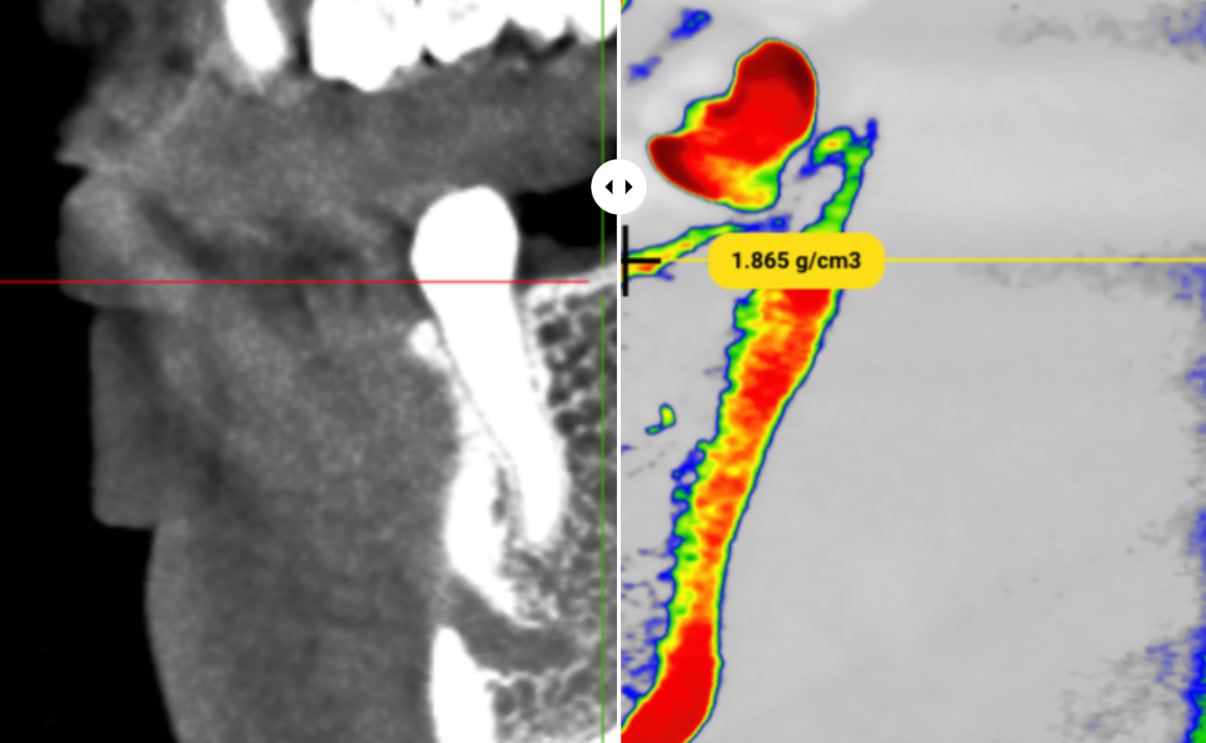

Visual Tech-lab showcased their SimDensity platform at IDS 2025, offering a AI-powered bone density measurement technology using existing CBCT data with a proprietary bone density phantom standard.

The technology analyzes CBCT scans to provide quantitative bone density measurements particularly valuable for pre-operative implant planning. Beyond implantology, SimDensity offers applications in orthodontic treatment planning for both clear aligner and traditional bracket systems, helping identify potential limitations or considerations related to bone density before initiating tooth movement.

What makes the system particularly practical is its seamless integration with existing CBCT technology without requiring additional patient radiation exposure. The cloud-based platform approach allows for implementation without significant hardware investments or workflow disruptions.

SimDensity represents another example of how artificial intelligence is extracting more clinical value from existing diagnostic imaging, providing quantitative data points that enhance evidence-based treatment decisions and potentially improve predictability of outcomes.